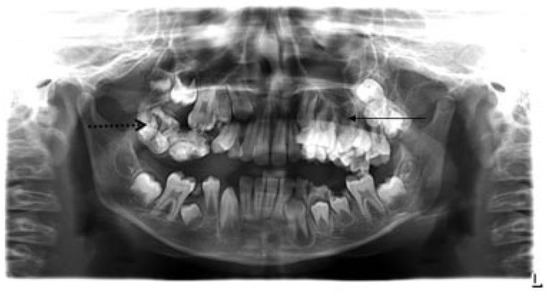

- Incomplete Tessier 7 soft tissue facial cleft and a complete skeletal Tessier 7 cleft on the right side

- Incomplete Tessier 5 skeletal and soft tissue Tessier 6 facial cleft on the left side